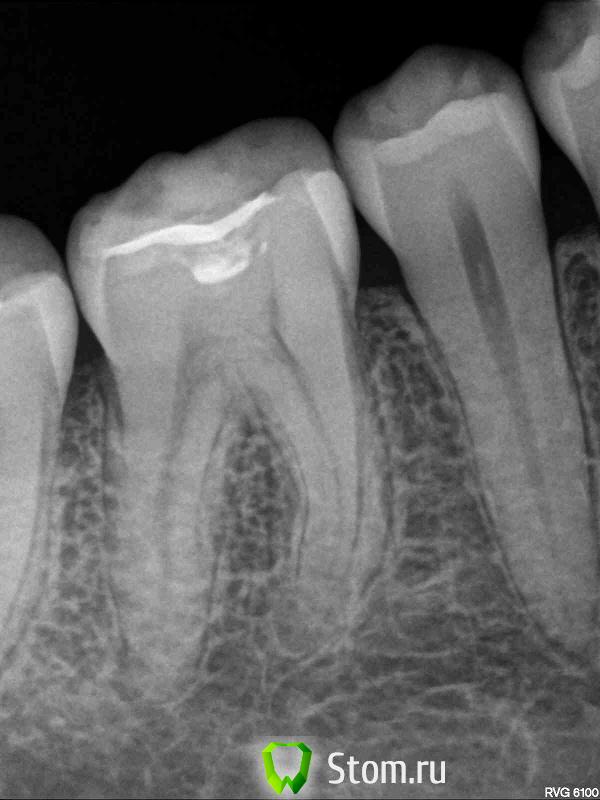

Anna_M Опубликовано 3 мая, 2012 Автор Поделиться Опубликовано 3 мая, 2012 17 зуб по орто странно выглядит. Что на нём фиксировано? Нет признаков расцементировки? Сама попробуй сделать пробу с горячей водой-возьми ватный шарик(небольшой, чтобы соседние зубы не задевал), смачивай его в очень горячей воде и прикладывай последовательно к шейкам 17, 46, 47. Почему 48 оставили ортодонты-тоже непонятно. Карман дистально от 47 есть?Татьяна, большое спасибо за ответ! Скажите, пожалуйста, какие подозрения вызвала у Вас семерка? На нем фиксирован брекет с накусочной площадкой на бугре и вестибулярная кнопка. Расцементировки нет, все спокойно вроде бы с этим зубом. Температурную пробу сделала. Реагирует на горячее, однозначно, 46, причем, только в том месте, которое на фото отмечено стрелкой (медиально-щечный бугор?), не сразу даже смогла определить вообще, какой зуб дает такую ужасную боль. 47 и 17 - все спокойно. 46 в других точках (сбоку, сверху, с обратной стороны) - тоже. Таки пропущен, наверное, какой-нибудь МБ2. Почему не удалили 48... пути ортодонтовы неисповедимы Кармана между 48 и 47 нет, вроде. На всякий случай сделала сегодня снимки, может быть, на них что-то будет видно. На 17 - коричневое пятно, которое я обнаружила сама, когда делала фото. Терапевт на этот счет сказал, что это кариес в стадии хронического пятна и его пока трогать не нужно. На снимке 47 видна какая-то подозрительная полость на жевательной поверхности, но доктор сказал, что это просто трещина в пломбе и разбираться с ней будем после снятия брекетов. Мне кажется, что там не только не пломбе трещина, но и на эмали между щечными буграми Прикрепляю снимки и фото всех "фигурантов" )) 46:http://uploads.ru/t/u/R/r/uRrVh.jpg 47:http://uploads.ru/t/I/w/V/IwVDY.jpg 17-47-46:http://uploads.ru/t/Z/u/Y/ZuYD3.jpg 17:http://uploads.ru/t/7/a/y/7aycH.jpg 46-47:http://uploads.ru/t/f/i/Q/fiQzC.jpg Ссылка на комментарий

Anna_M Опубликовано 4 мая, 2012 Автор Поделиться Опубликовано 4 мая, 2012 Впрочем, с 48 вопрос уже почти решен и без одобрения ортодонта. Даже почти договорилась с одним хорошим доктором ). Мне бы сначала с более насущными проблемами разобраться, например с болью этой, вообще уже есть невозможно, даже едва теплую пищу. И боль при накусывании появилась в этой области. Подскажите, пожалуйста, что нужно делать? Реэндо 46? А с трещиной на 47 и правда можно повременить до снятия брекетов (около4-6 мес. еще носить по самым оптимистичным прогнозам, а возможно, и дольше). Кстати, в той же злополучной области 46-47 есть еще реакция на сладкое (не такая адская, как от горячего, но достаточно неприятная), причина в трещине на 47, или какая-то другая? Хелп! Ссылка на комментарий

Scrabble Опубликовано 4 мая, 2012 Поделиться Опубликовано 4 мая, 2012 На сладкое зуб с кариесом реагирует. А причиной болей от горячего может быть пропущенная анатомия в 46. Хотя с реэндо я бы повременила до удаления 48( а вдруг всё-таки причина этих злополучных болей именно взаимотношение дистальной поверхности корня 47 и бугров 48) Ссылка на комментарий